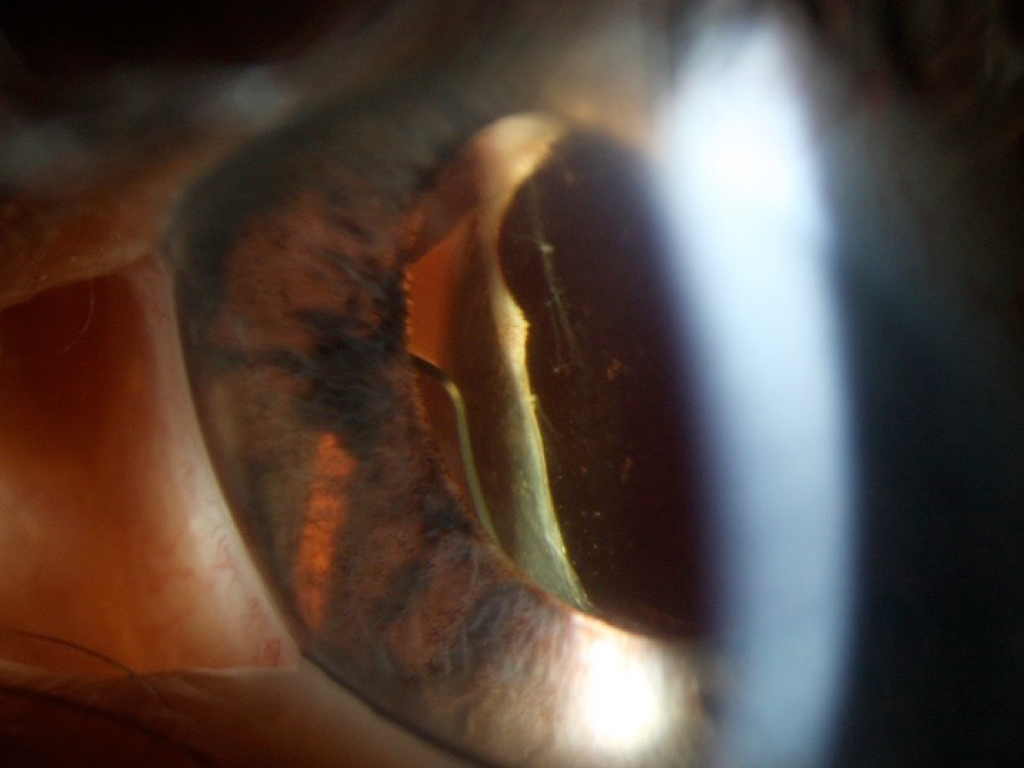

One piece acrylic intraocular lens is placed in the sulcus and one of lens haptics is causing chaffing of iris. Photo: Courtesy of Sunir Garg, MD